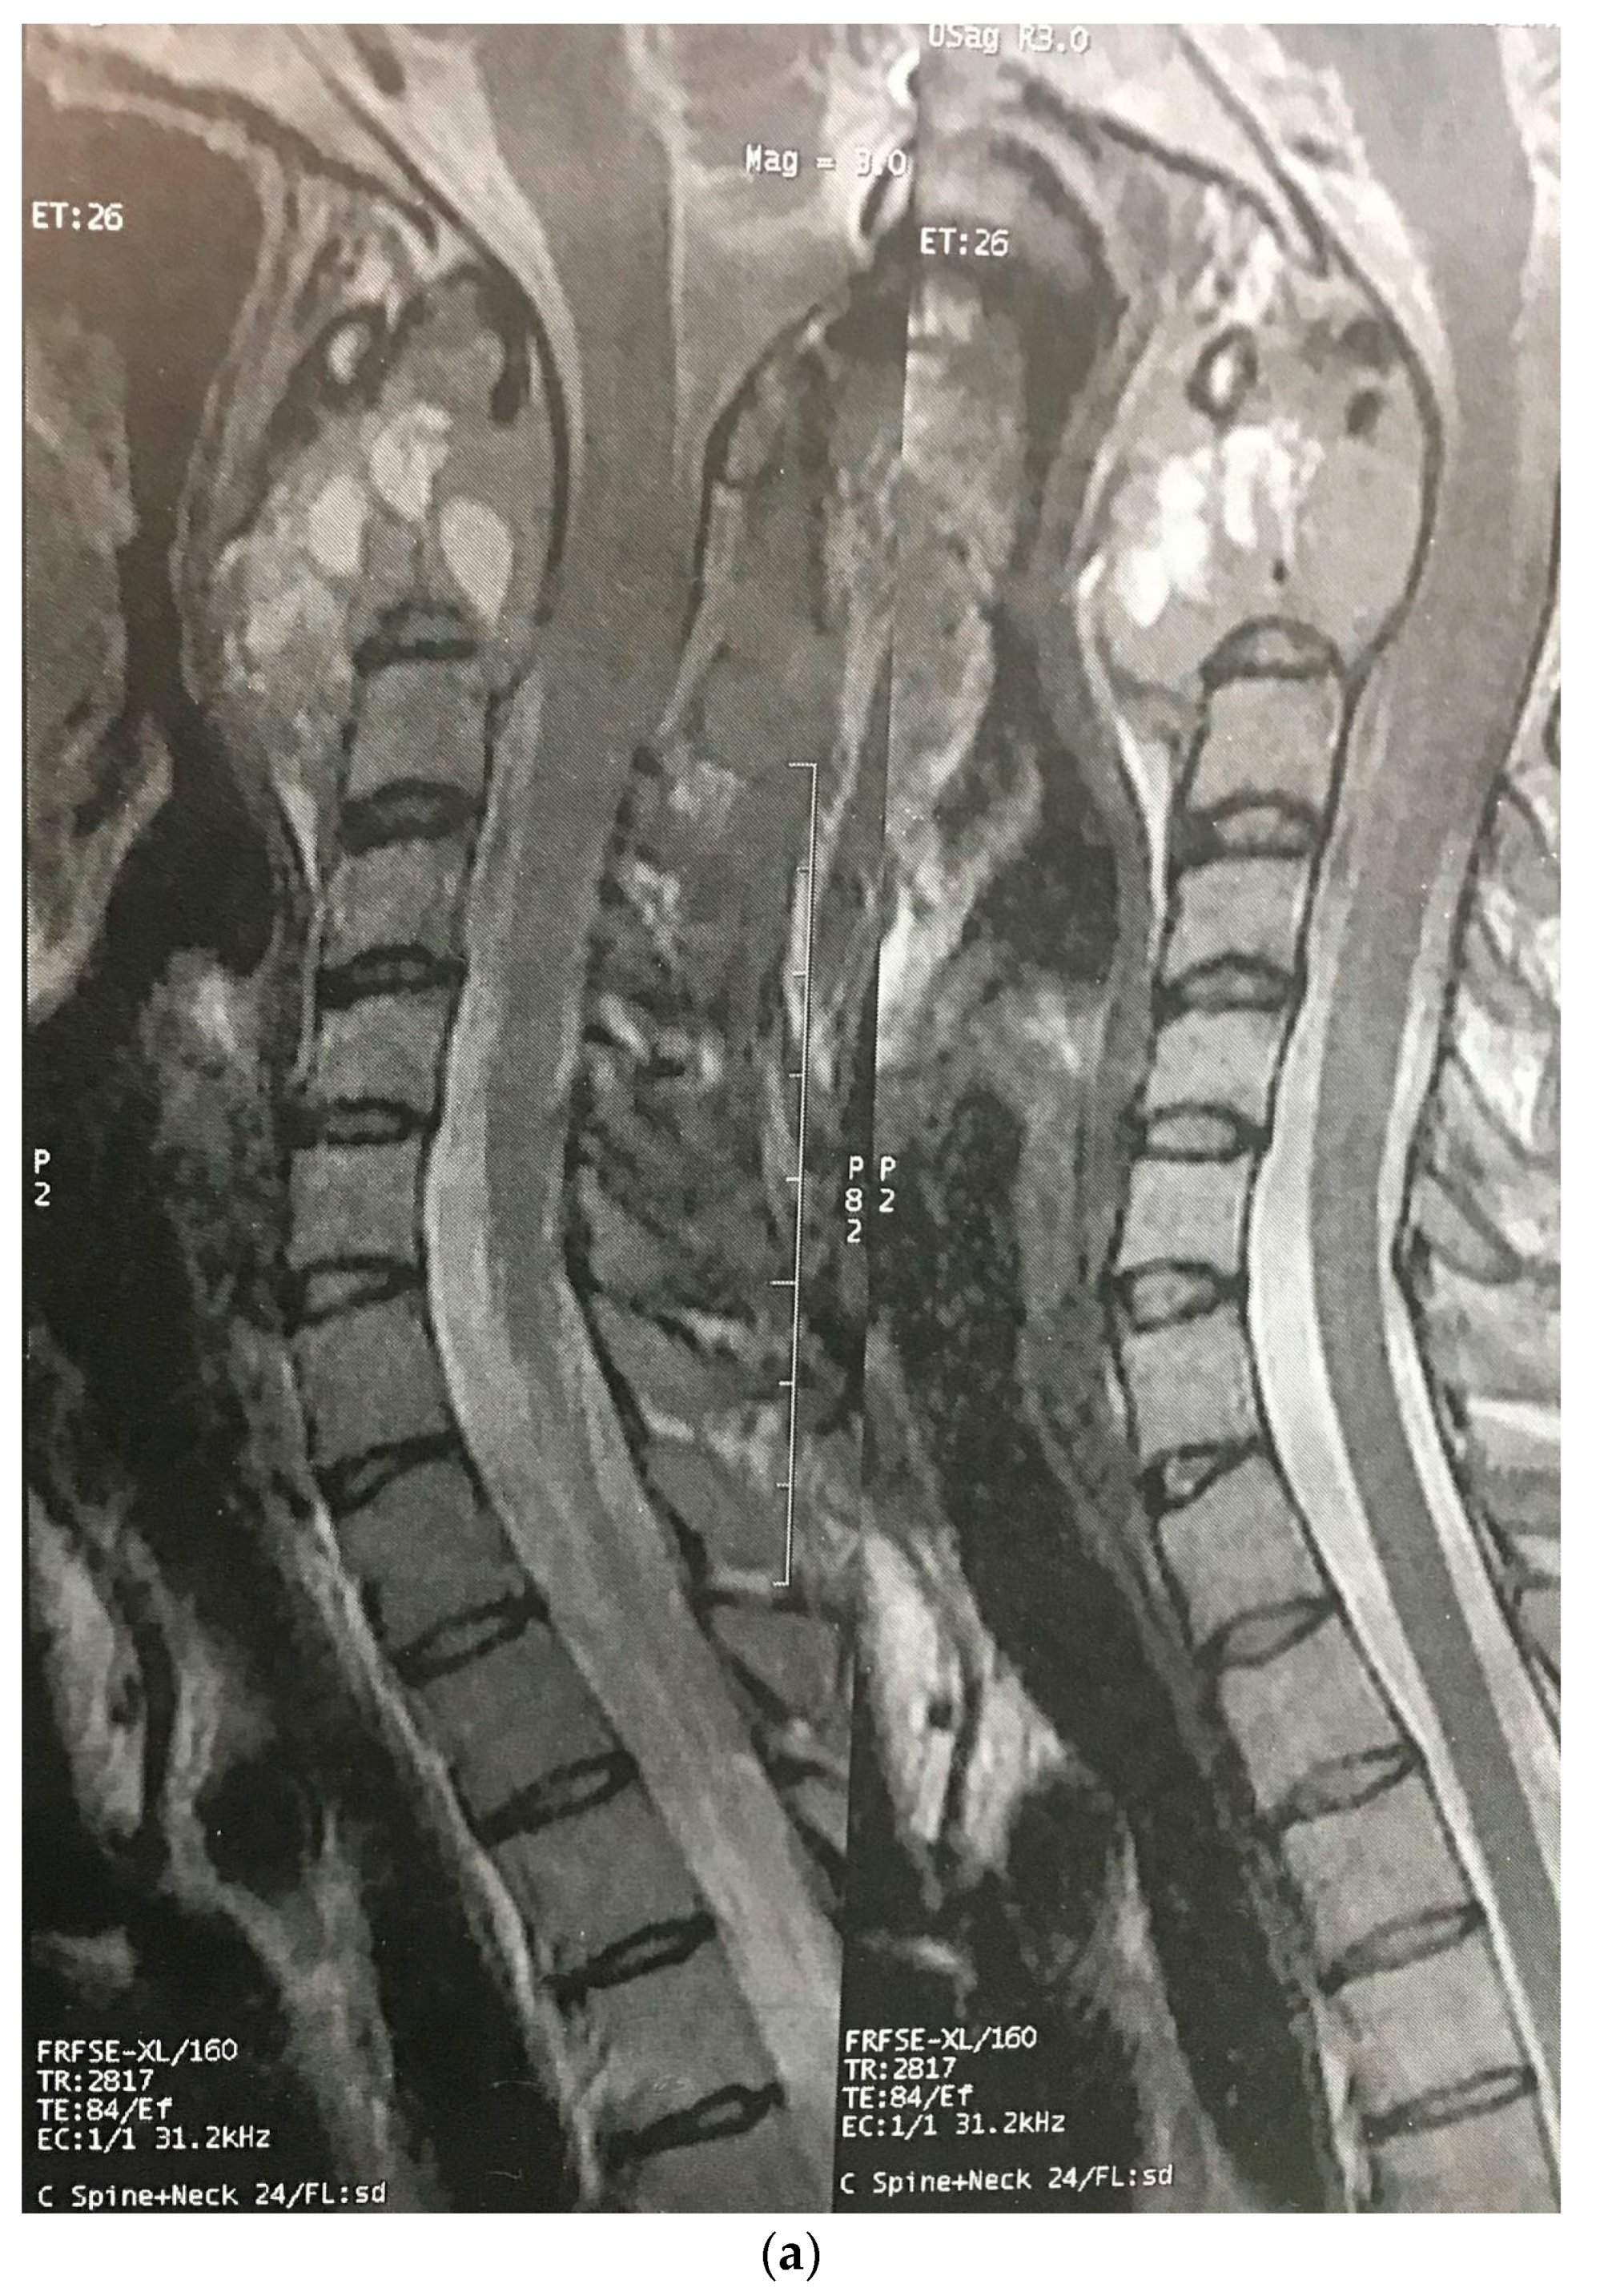

The patient was a 29-year-old female with an initial complaint of neck pain and limited mobility. In a cervical CT scan, the complete destruction of the second cervical vertebra was obvious. In the MRI of the cervical spine, a large heterogenous tumoral mass in the C2 vertebra with some necrotic/cystic parts and a marked paravertebral extension was seen. It was almost isointense to the cord in the T1W and T2W images and was heterogeneously enhanced with gadolinium (Figure 1). The thoracic and lumbar MRI and the thoracic and abdominal CT scans were normal.

Figure 1.

Sagitta (a) and axial (b) gadolinium-enhanced MRI showing the tumor in the C2 body.